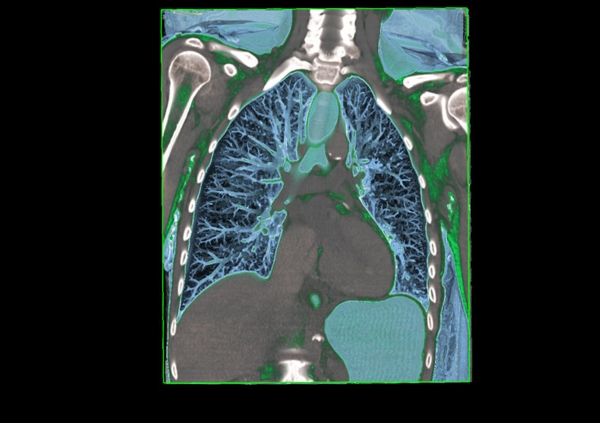

在随后的幻灯片中,您将看到来自瑞典医学图像科学与可视化中心(the Center for Medical ImageScience and Visualization ,CMIV)的Anders Persson和他的同事们运用CT,MRI和超声得到的令人惊叹的尸检图片。这些图片描绘了人体骨骼,消化道,循环系统和大脑以及野猪的前端结构。

5, 人体,正俯视;肺内结构清晰可见。